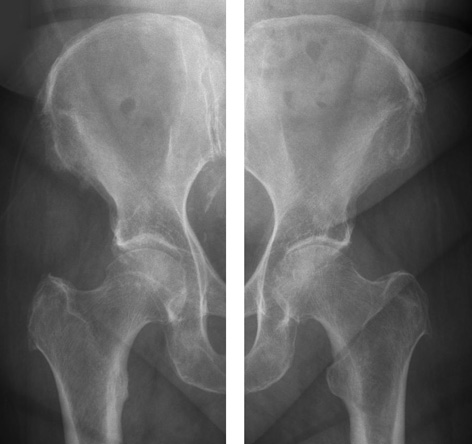

Der häufigste Grund, ein künstliches Hüftgelenk einzusetzen, ist altersbedingter Verschleiß des Gelenkes. Dabei verschleißt nicht der Knochen, sondern der Knorpel, der die Gleitschicht des Gelenkes bildet. Gelenkknorpel kann man grundsätzlich auf Röntgenbildern leider nicht erkennen. Aber der Abstand zwischen dem Hüftkopf und der Hüftpfanne zeigt, wie kräftig die Knorpelbeschichtung noch ist. Beim gesunden Hüftgelenk sind das ca. 8 Millimeter, also etwa 4mm Schicht auf dem Hüftkopf und 4 mm Schicht in der Hüftpfanne.

Auf dem Röntgenbild unten links ist ein Hüftgelenk zu sehen, das zwar schon nicht mehr ganz gesund ist, aber noch keinen so starken Verschleiß zeigt wie auf dem rechten Bild. Das rechte Bild zeigt eine fortgeschrittene Hüftgelenkarthrose, der Spalt zwischen Kopf und Pfanne ist zum Teil kaum noch zu erkennen.